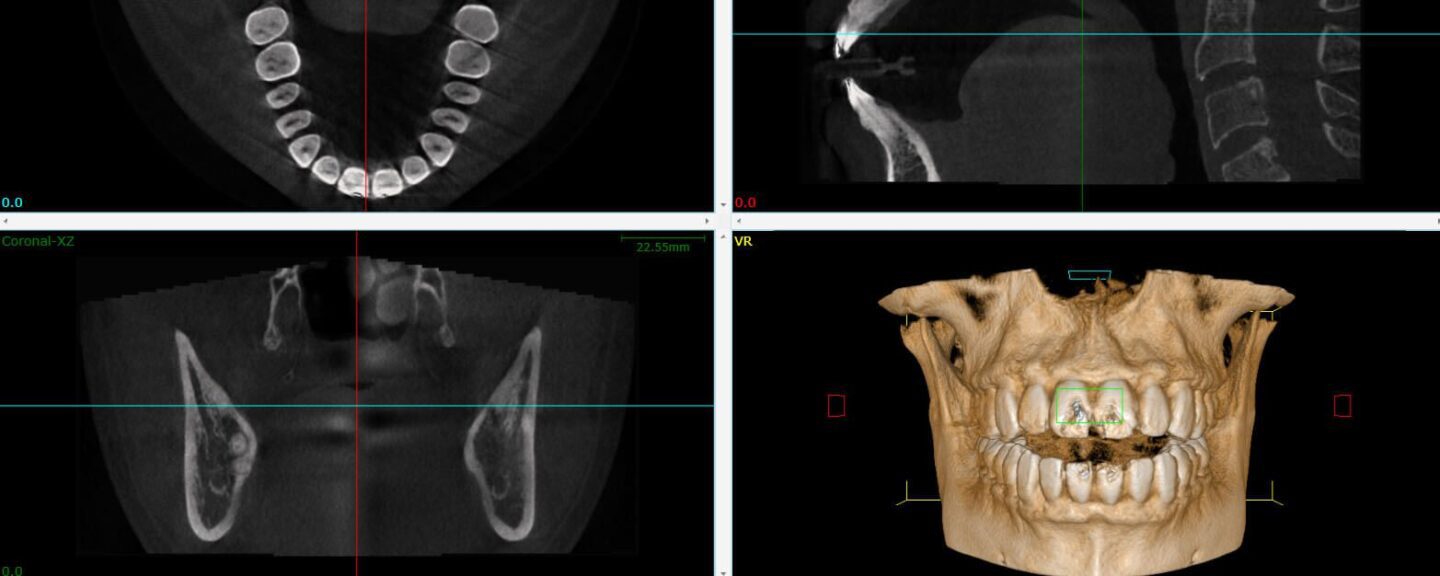

Contents Technology Deep Dive: 3D Cbct Scan Price Techn […]

Contents Technology Deep Dive: 3D Cbct Scan Technical B […]